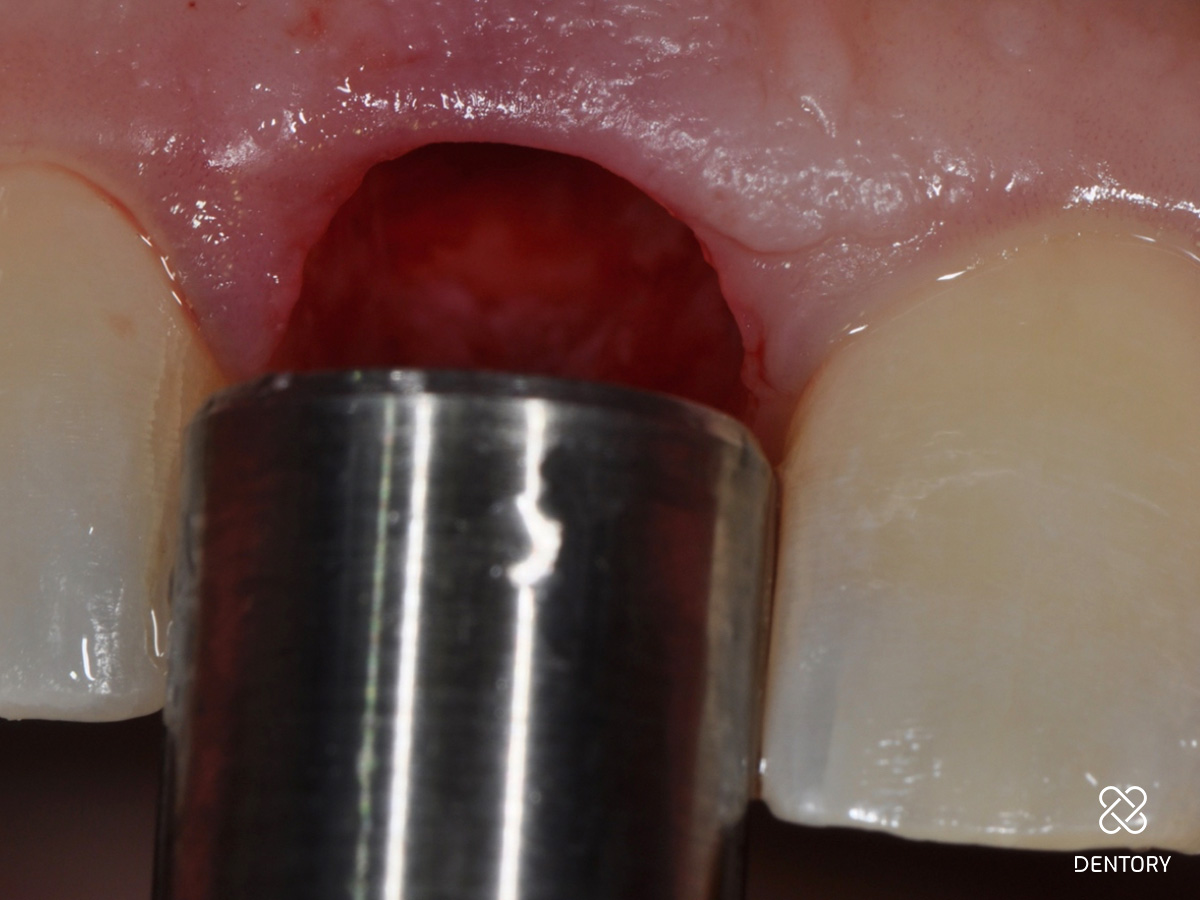

Abbildung 10

Aus der Tuberregion wird nun distopalatinal des zweiten Molaren in einer Dicke von etwa 4 mm mit einer maschinellen Gewebestanze ein freies Gingivatransplantat entnommen.

Abbildung 11

Mit einem scharfen Instrument werden die Fasern durchtrennt, sodass Periost und bindegewebige Fasern am Knochen verbleiben. Dadurch wird eine Exposition des Knochens vermieden und die Heilung beschleunigt.